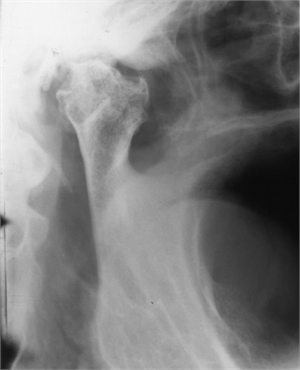

Transcranial Xray imaging

Transcranial X-ray

This is a radiograph taken in both open and closed mouth positions. The x-ray beam is directed from the opposite side of the TMJ of interest. It is placed behind and upwards the ear and angulted such that it coincides with the centre of the TMJ of interest. This radiograph sees many  structures overlapping each other due to which it is often contradicted. However, it can correctly help in diagnosing fractures of the condyle (portion of the mandible that attaches to the temporal bone) and any changes in the width of the bone.